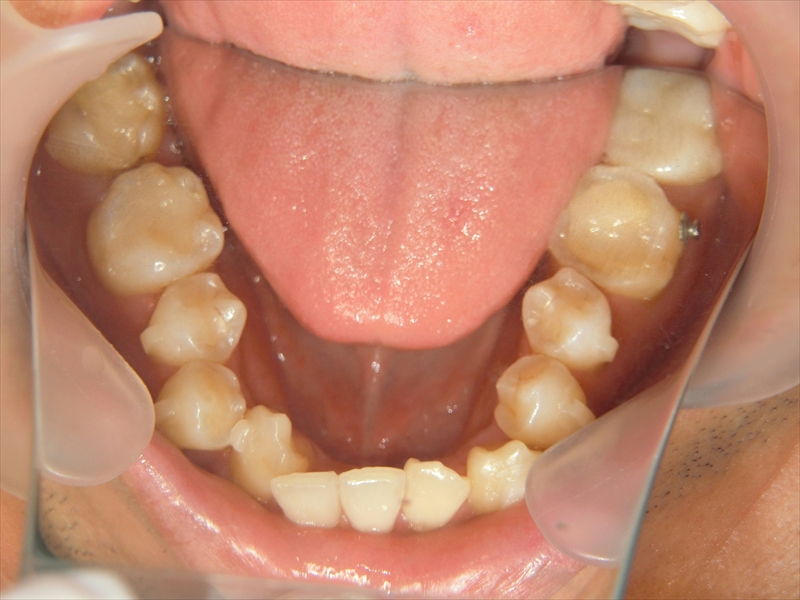

下の歯は、受け口気味で、さらに右下の前から2番目の歯が1本足りない状態でした。

また、歯並び全体がお顔の中心よりも右にずれており、噛み合わせも左右で違っていました。

このような状態を改善するため、歯を同じ方向に動かすのではなく、左上の奥歯は後ろへ、右下の奥歯も後ろへと、斜め方向に歯を動かす治療計画を立てました。

これにより、歯並びのズレや噛み合わせの左右差を少しずつ整えていきました。

治療前後 写真